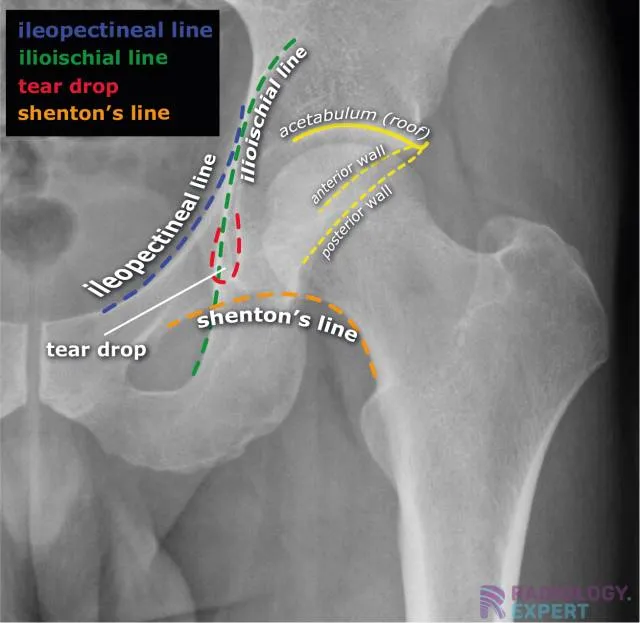

Key Radiographic Lines - Connect the Dots

Shenton's Line: A smooth, continuous arc from the medial aspect of the femoral neck to the inferior border of the superior pubic ramus. Disruption is a key sign of a femoral neck fracture or developmental dysplasia of the hip (DDH).

Iliopectineal Line: Follows the pelvic brim, representing the anterior column of the acetabulum. A break suggests an anterior column fracture.

Ilioischial Line (Kohler's Line): Represents the posterior column of the acetabulum. Disruption points to a posterior column fracture.

⭐ A subtle break in Shenton's line can be the only radiographic evidence of an undisplaced or impacted femoral neck fracture, a frequent injury in osteoporotic elderly patients.

Acetabular Landmarks - Hip Socket Scoop

- Iliopectineal Line: Represents the anterior column.

- Ilioischial Line: Represents the posterior column.

- Radiographic Teardrop: Formed by the medial wall of the acetabulum.

- Shenton's Line: A continuous curve along the inferior border of the femoral neck and the superior pubic ramus. Disruption suggests fracture or dislocation.

- Acetabular Roof (Sourcil): The weight-bearing dome.

⭐ Disruption of Shenton's line is a classic sign of a femoral neck fracture or developmental dysplasia of the hip (DDH).